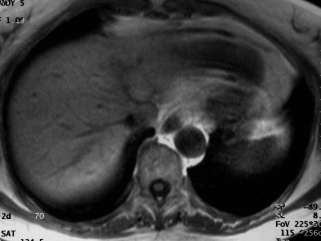

IRM T1 EG sans injection IRM T1 sans injection

La métastase prend le contraste en couronne mais celle-ci est assez régulière et surtout le contraste est moins intense que celui des vaisseaux. L'angiome est difficile à voir car les coupes sont artefactées par les mouvements cardiaques.